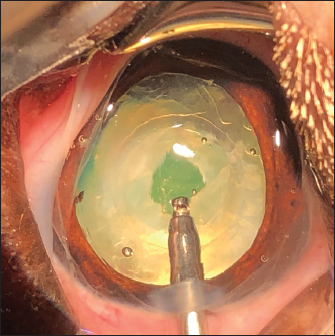

After 3.2-mm clear corneal incision using an angled microsurgical knife (Unique Technologies, Inc, Mohnton, USA) and inflation of the anterior chamber with 1.6% sodium hyaluronate viscoelastic substance (Ophteis Bio 1.6, Rayner, Worthing, UK), anterior capsulorhexis was performed. Then conventional phacoemulsification (Infiniti Vision System, Alcon Laboratories, Inc. Fort Worth, USA) using a one-handed technique was completed, followed by meticulous irrigation-aspiration of the residual cortical material and polishing of the posterior capsule (PC). At this stage, a marked PCO obstructing the visual axis was found in five cases (Fig. 2), previously diagnosed by ultrasound in the sixth. In order to restore the transparency of the visual axis, an axial posterior capsulorhexis (APC) was performed in all cases, before or after implantation of an IOL (Intraocular implant PFI, Medicontur, Zsambék, Hungary). The IOL implantation inside the capsular bag was performed in a conventional manner using an injection cartridge through the limbal keratotomy. For the four cases implanted before APC, the approach of the PC was to inject viscoelastic gel into the capsular bag to mobilize the IOL (inside the bag) to access the PC, using two variations. The first method was to push and position the IOL laterally and obliquely toward the equator of the bag by gently injecting the viscoelastic gel, to reach the central area of the PC for the surgical approach (Fig. 3). A second method was to leave the IOL centered in the bag and inject the viscoelastic gel between the IOL and the PC, allowing visualization of the PC through IOL optic for its surgical approach under it. In all cases, the amount of gel injected was visually controlled by the degree of concave swelling of the PC to avoid overinflating it.

Fig. 3. Posterior capsulotomy after IOL lateral displacement toward the equator of the capsular bag: IOL in the bag, note the marked PCO (a). Injection of viscoelastic gel to move laterally the IOL inside the bag (b). Posterior capsulotomy (black arrow) (c).